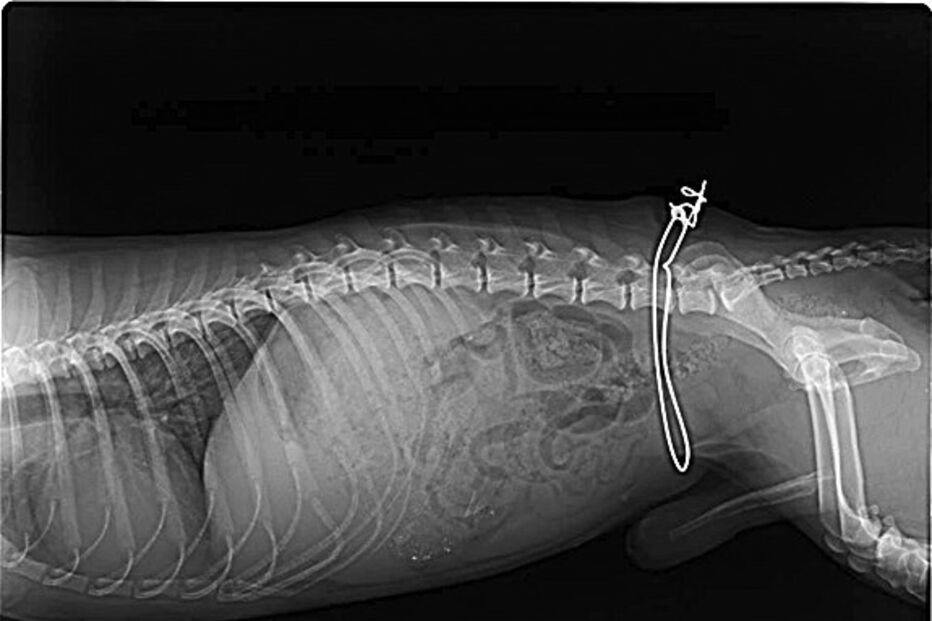

Arame, que ficou preso ao animal, já estava coberto pela pele.

A ADAPO - Associação de Defesa dos Animais e Plantas de Olhão recolheu um cão com uma armadilha de caça artesanal à volta do corpo, já no interior da pele. O animal tinha sido apanhado, há mais de um mês, na zona de Olhão, e como o arame do dispositivo ficou preso, começou a ser absorvido pelo corpo do animal. O cão já foi operado, com sucesso, e espera agora por uma casa de acolhimento.

"As voluntárias foram ao terreno e tiveram muitas dificuldades em recolher o cão, que estava muito medroso e agressivo, mas quando finalmente conseguiram, perceberam bem o grave estado em que estava", contou ao CM Célia Caravela, presidente da ADAPO. O animal não tinha conseguido libertar-se da armadilha de caça e já tinha o arame completamente envolto pela pele, que entretanto cobrira a ferida.

A cirurgia para retirar o arame foi realizada por um veterinário local e o cão, sem raça conhecida, está para adoção.